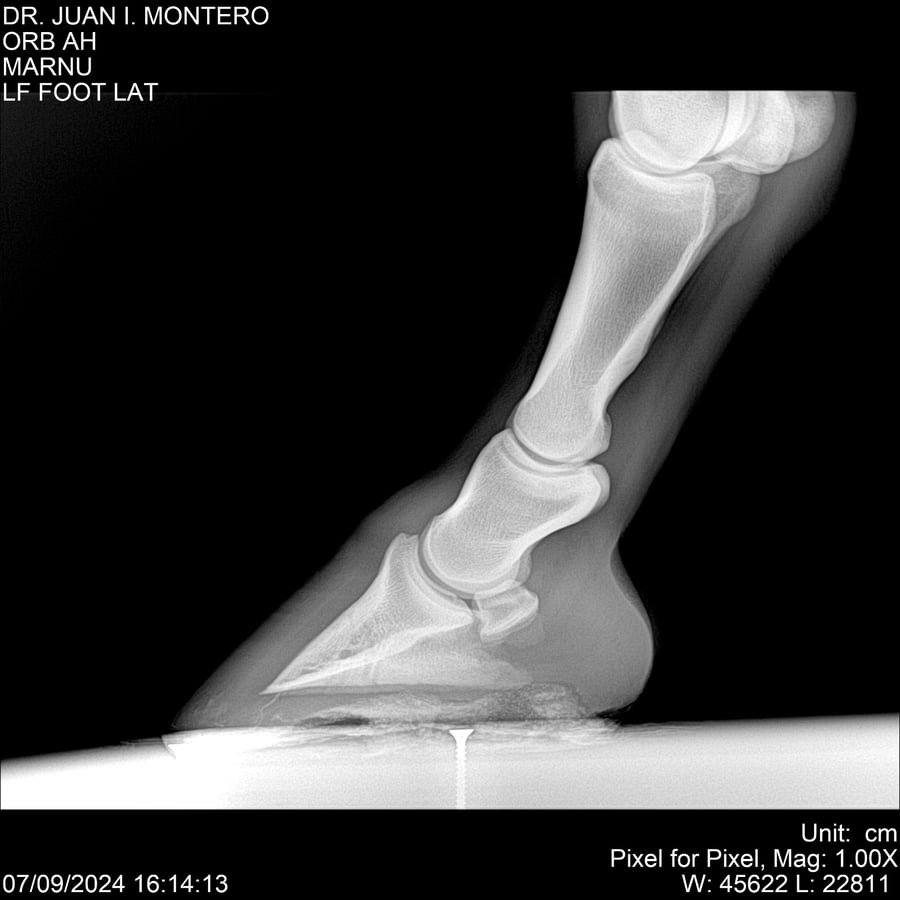

LOTE 21, ORB AH Lote Anterior Volver al remate Lote Siguiente Ficha Contacto Montevideo - Ficha del Lote Identificador: #282519 Categoría: Yeguarizos Montevideo - 57 Visualizaciones ClicData Contacto Empresa: Abelenda N. R., Walter Hugo Nombre*: Teléfono* : E-mail* : Mensaje Enviar Registrese gratis Este contenido Exclusivo está disponible sólo para usuarios registrados Ingresar